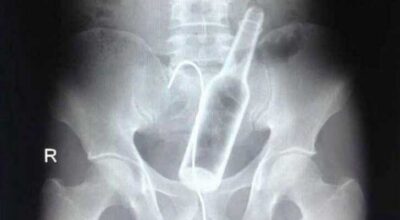

Esta recopilación de imágenes recoge alguna de las situaciones más estrambóticas que se han podido dar en una sala de rayos X. Todas ellas tienen algo en común: Son objetos extraños para el cuerpo humano que, de alguna manera han encontrado una vía de entrada, pero se han perdido a la hora de encontrar la de salida.

Muñecas de juguete descabezadas, botellas, armas, frascos, botes de plástico, teléfonos y hasta una cinta de casete pueden encontrarse en esa suerte de “punto limpio” al que ha quedado reducido el interior de los afectados.

No sabemos, ni juzgamos, la forma o los motivos por los que terminaron atrapados en dichas partes del cuerpo, pero estamos convencidos de que algún doctor estuvo al borde de la carcajada cuando se encontró con casos tan llamativos e inverosímiles como estos ¡Ver para creer!